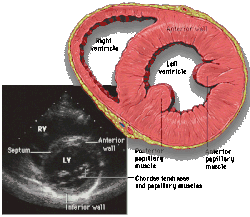

Parasternal short axis

Each figure contains a TTE with a black background, and a corresponding colored illustration. Patrick J. Lynch and C. Carl Jaffe, Yale University, 2006.

Click on a figure to enlarge it and see some parts of the heart identified. RV, right ventricle; LV, left ventricle; RA, right atrium; LA, left atrium; TV, tricuspid valve; MV, mitral valve; AV, aortic valve; RVOT, right ventricular outflow tract; LVOT, left ventricular outflow tract